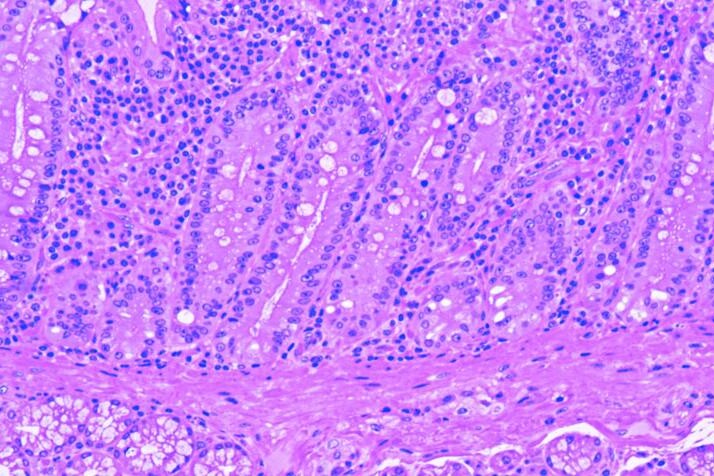

Nejvnitřnější vrstvou stěny dvanáctníku je samotná sliznice. Ve sliznici jsou žlázy produkující zásadité výměšky s obsahem trávicích enzymů. Výměšky neutralizují žaludeční kyselinu. Buňky sliznice dvanáctníku se nepřetržitě nahrazují, dělí se mnohem rychleji než ostatní buňky v lidském těle - každou hodinu se obmění asi 1 % slizničních buněk.